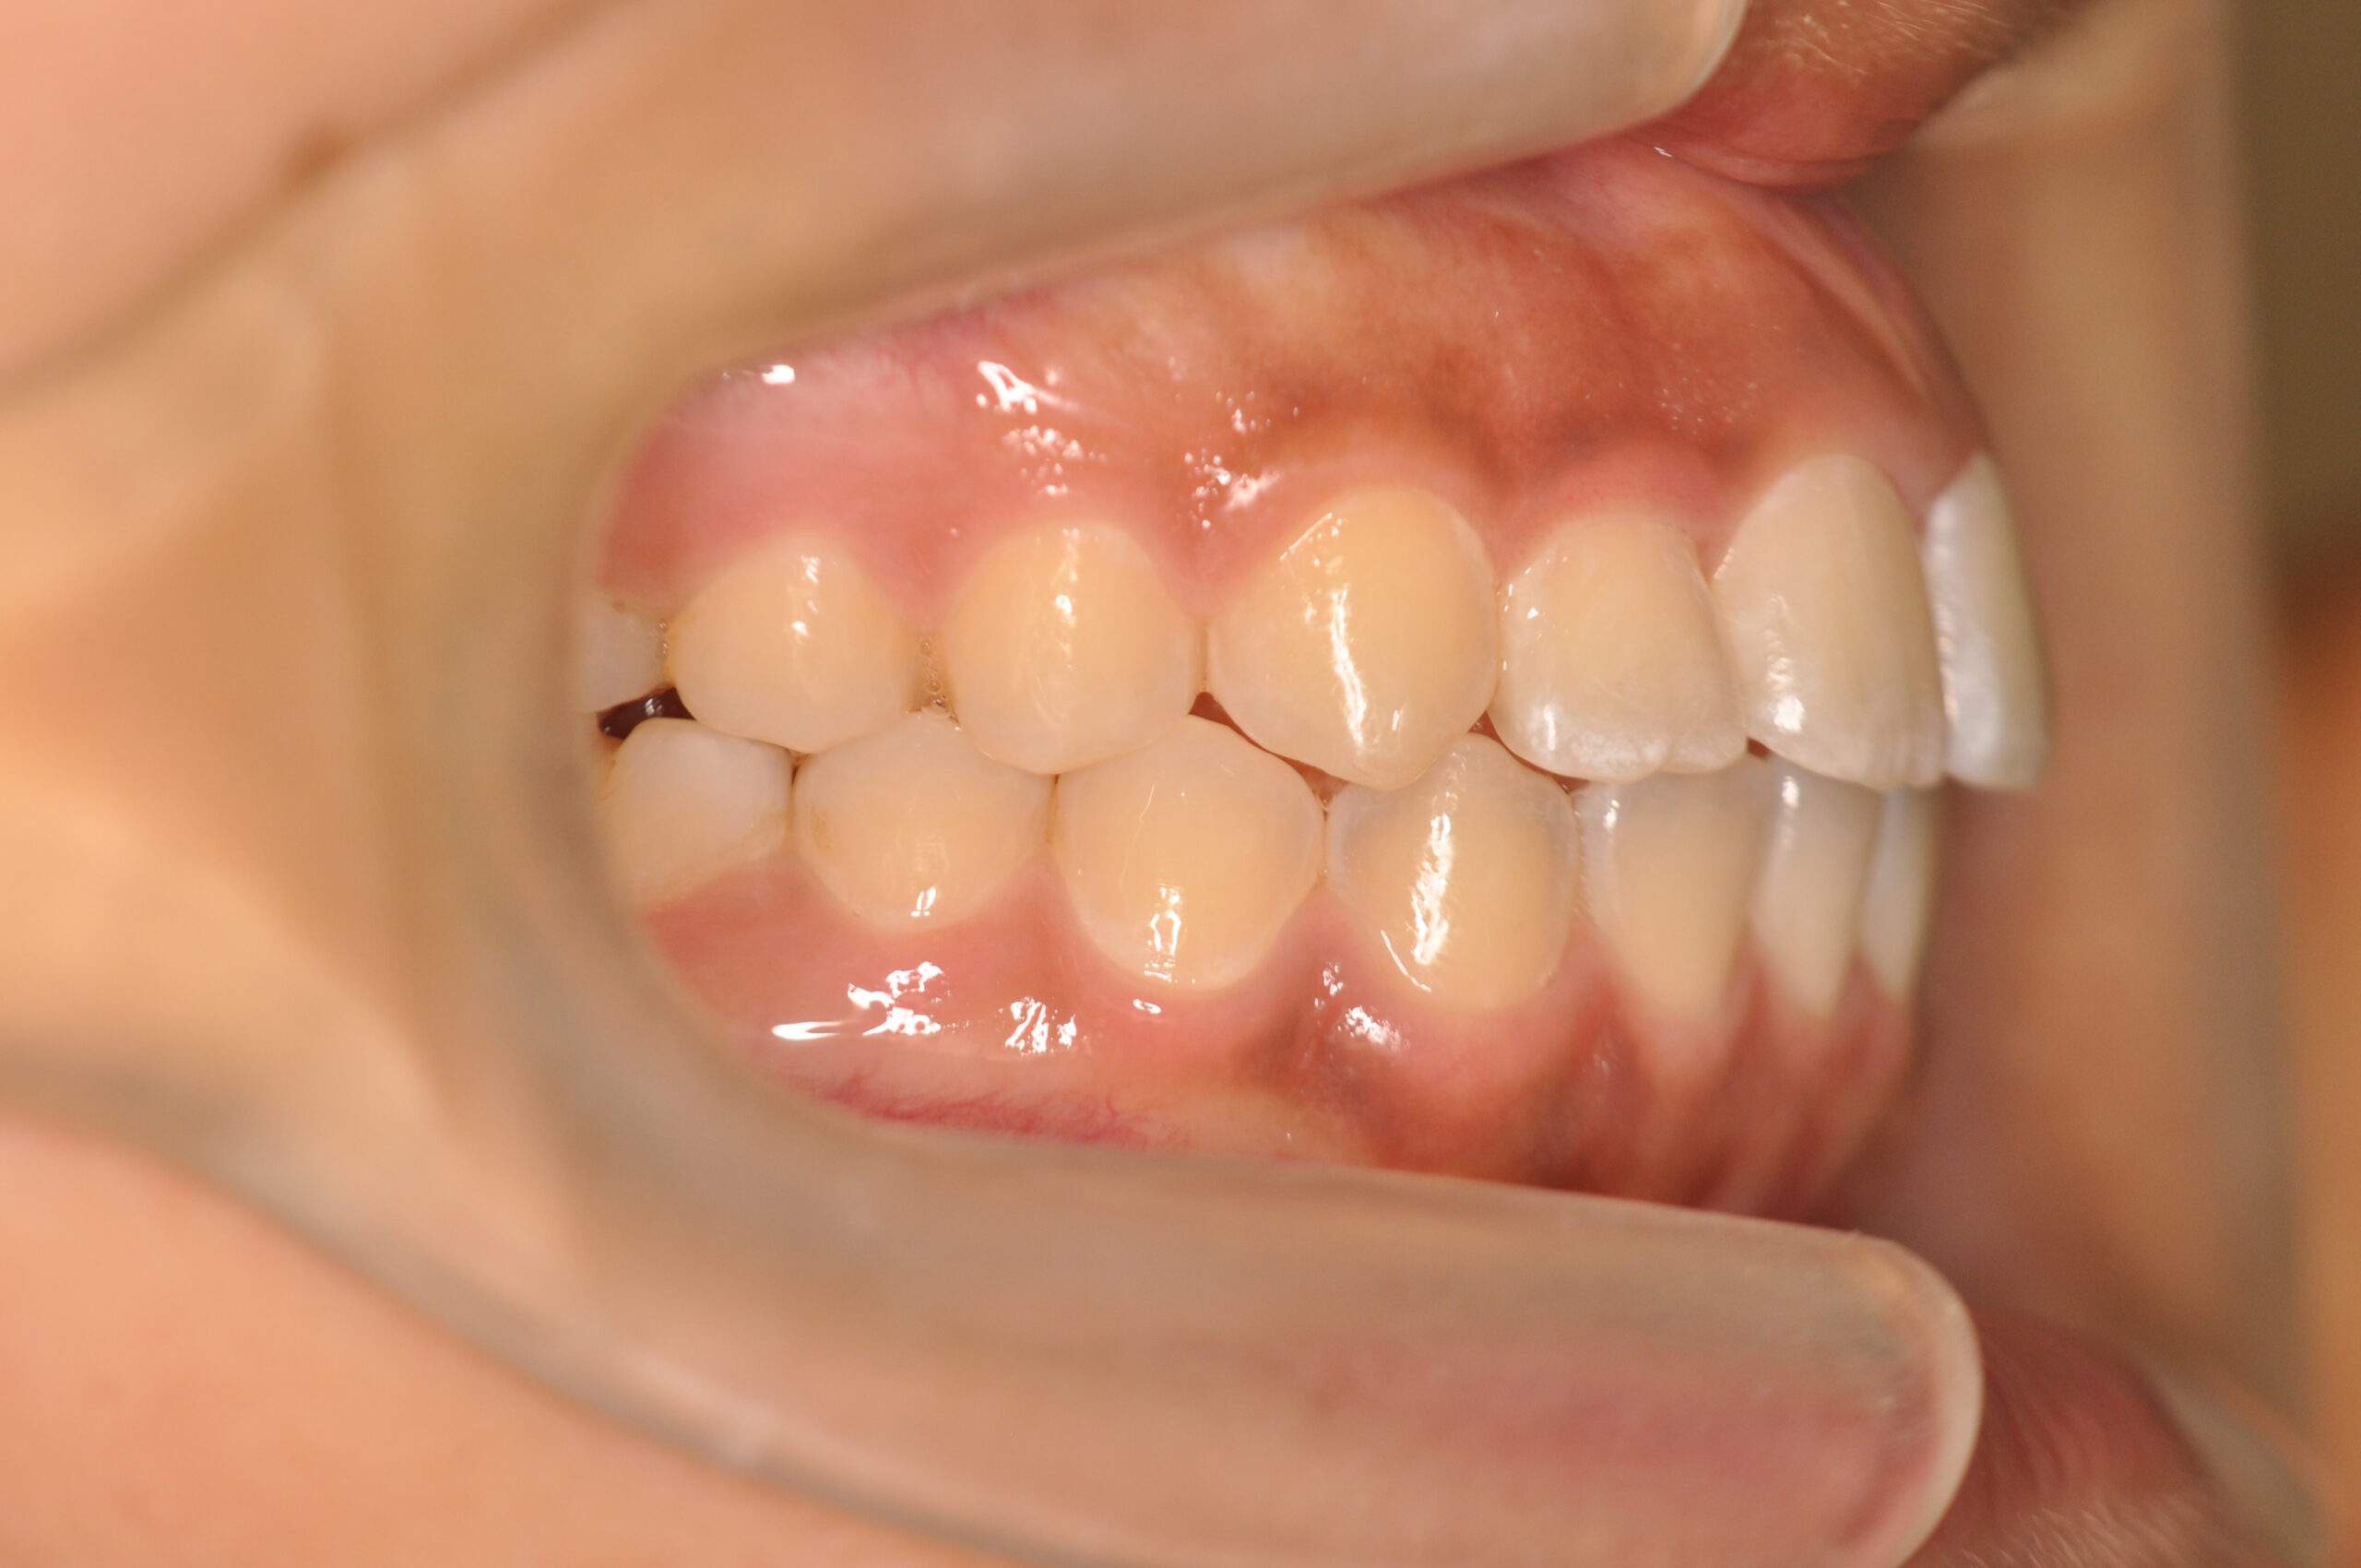

| 治療内容の詳細 | 初診時14歳の女性で、歯のがたつき、かみ合わせを気にされ来院されました。 検査の結果、上下顎前歯部叢生および開咬を伴うアングルⅠ級不正咬合と診断しました。 治療としては、非抜歯の上、セルフライゲーションブラケット装置(デーモンシステム)と マウスピース矯正装置(インビザライン)で配列を行いました。 開咬については、顎間ゴムの協力もあり改善されました。 治療期間は、2年2ヶ月でした。 |